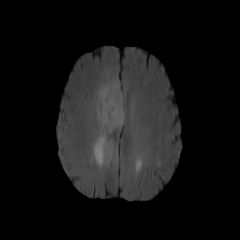

The Conditional Random Field as a Recurrent Neural Network layer is a recently proposed algorithm meant to be placed on top of an existing Fully-Convolutional Neural Network to improve the quality of semantic segmentation. In this paper, we test whether this algorithm, which was shown to improve semantic segmentation for 2D RGB images, is able to improve segmentation quality for 3D multi-modal medical images. We developed an implementation of the algorithm which works for any number of spatial dimensions, input/output image channels, and reference image channels. As far as we know this is the first publicly available implementation of this sort. We tested the algorithm with two distinct 3D medical imaging datasets, we concluded that the performance differences observed were not statistically significant. Finally, in the discussion section of the paper, we go into the reasons as to why this technique transfers poorly from natural images to medical images.